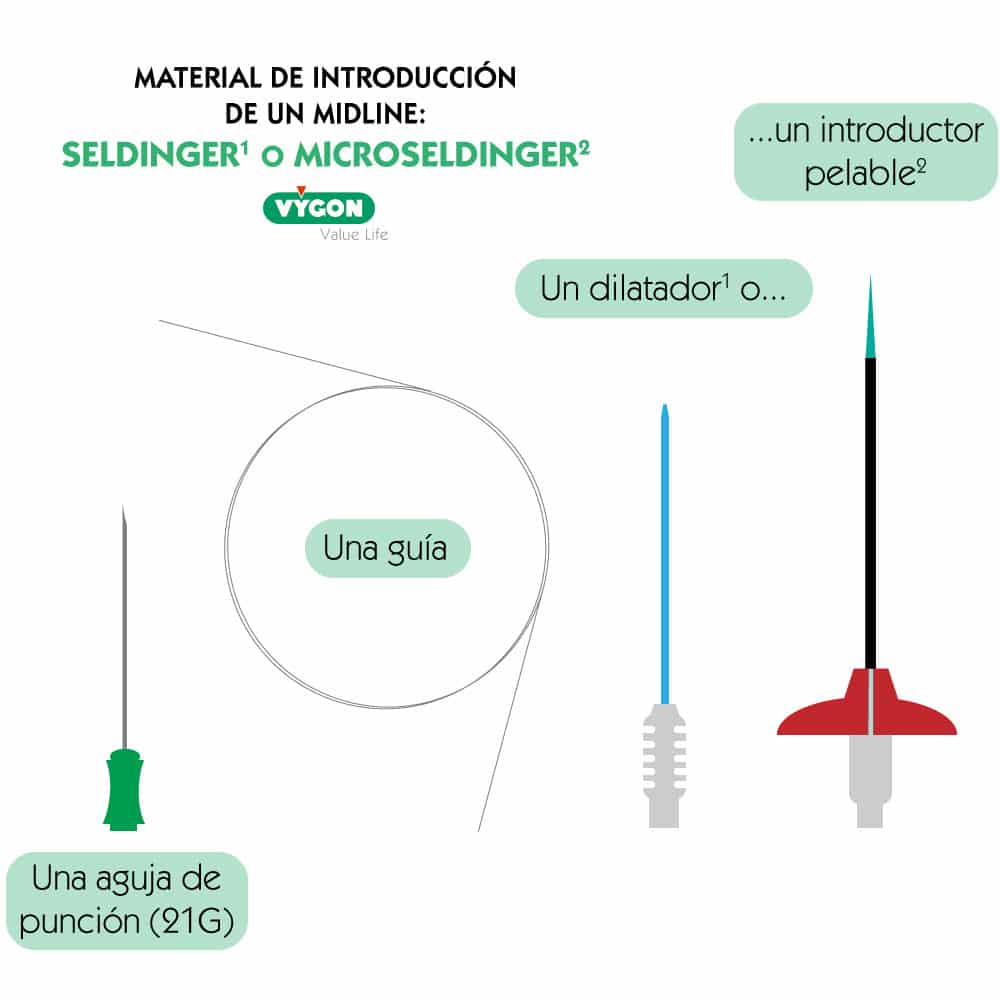

Una línea media se inserta con técnica Seldinger: es conocida en las UCI por ser el método de introducción de las vías centrales y de los catéteres arteriales.

La técnica Seldinger puede ser pura, simplificada o modificada.

Para ello, se necesita:

- una aguja de punción fina, en general de 21G

- una guía de acero inoxidable o de nitinol (material antiacodamiento)

- un dilatador que sirve únicamente para la dilatación o

- un microintroductor que consta de una vaina pelable y de in dilatador interno.

La ventaja de cualquiera de las técnicas Seldinger es que la aguja sirve solo para localizar la vena. La guía sirve para canalizar la vena y guiar el catéter. Se trata de la técnica “over the wire” = encima de la guía. Al no tener el catéter junto a la aguja, no se necesita canalizar en el momento de la punción, significa que el gesto se hace en varias etapas y de esta forma es mucho menos invasivo.

Se usa una aguja de calibre pequeño para poder minimizar el trauma a los tejidos. Sin embargo, el uso del dilatador es necesario cuando el diámetro del catéter es superior al orificio que crea la aguja. Sirve para ensanchar el paso subcutáneo.

• La técnica Seldinger pura es la técnica con dilatación

• La técnica Seldinger simplificada es la técnica sin dilatación

• La técnica Seldinger modificada (o MicroSeldinger) es la técnica con introductor pelable, que lleva en su interior un dilatador que se deja. Entonces se quita la guía y el dilatador interno. De esta forma, el introductor sirve de guía para insertar el catéter.